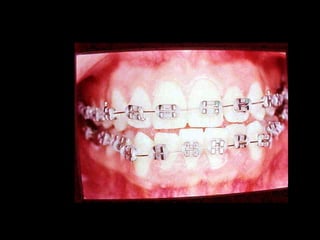

Eliminación de rotaciones. Correcciónde las discrepancias de longitud de arco. Posición de los incisivos y molares por medio del torque adecuado. Llevar cualquier otra alineación en el arco. Eliminación de rotaciones. Corrección de las discrepancias de longitud de arco. Posición de los incisivos y molares por medio del torque adecuado. Llevar cualquier otra alineación en el arco.

Evita el potencialde recidiva Aumenta la velocidad y eficacia del tratamiento

Maxilar: Retenedor de Howley,sin interferencias oclusales. Mandíbula: Retenedor fijo de canino a canino Maxilar: Retenedor de Howley, sin interferencias oclusales. Mandíbula: Retenedor fijo de canino a canino